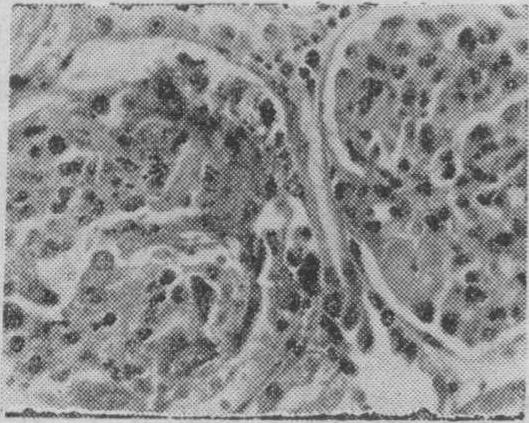

病肾的急性期病变主要为增殖性肾炎,伴有蛋白质渗出(图1)。数周后肾小球内新月体形成(图2),逐渐发展为整个小球纤维化及玻璃样变(图3)。电镜检查肾小球基膜增厚、破裂,沿肾小球基膜内皮细胞下有电子致密物沉积(图4)。免疫荧光检查肾小球及部分肾小管基膜上有免疫球蛋白(在第一阶段只有异体的,第二阶段又加上自体的)及补体,有时还有纤维蛋白原呈均匀的线条状沉积。

图1肾小球肿胀,内皮细胞及系膜细胞增生(H. E.×500)